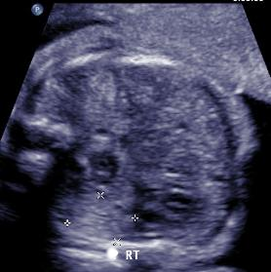

Above. Case 3. 28 3/7 weeks gestation. Cystic mass in the right upper quadrant measuring 5.9 x 2.9 x 3.4 cm. The cyst is posterior to the right lobe of the liver and extends inferiorly.

Above. Case 3. 28 3/7 weeks gestation. Transverse view of a cyst in the right upper quadrant.